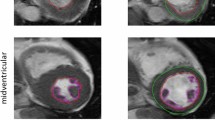

Machine learning techniques designed to recognize views and perform measurements are increasingly used to address the need for automation of the interpretation of echocardiographic images. The current study was designed to determine whether a recently developed and validated deep learning (DL) algorithm for automated measurements of echocardiographic parameters of left heart chamber size and function can improve the reproducibility and shorten the analysis time, compared to the conventional methodology. The DL algorithm trained to identify standard views and provide automated measurements of 20 standard parameters, was applied to images obtained in 12 randomly selected echocardiographic studies. The resultant measurements were reviewed and revised as necessary by 10 independent expert readers. The same readers also performed conventional manual measurements, which were averaged and used as the reference standard for the DL-assisted approach with and without the manual revisions. Inter-reader variability was quantified using coefficients of variation, which together with analysis times, were compared between the conventional reads and the DL-assisted approach. The fully automated DL measurements showed good agreement with the reference technique: Bland–Altman biases 0–14% of the measured values. Manual revisions resulted in only minor improvement in accuracy: biases 0–11%. This DL-assisted approach resulted in a 43% decrease in analysis time and less inter-reader variability than the conventional methodology: 2–3 times smaller coefficients of variation. In conclusion, DL-assisted approach to analysis of echocardiographic images can provide accurate left heart measurements with the added benefits of improved reproducibility and time savings, compared to conventional methodology.